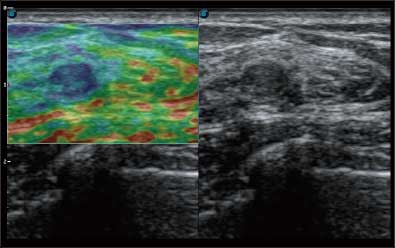

微米成像技术提升了对组织斑点噪声信号的抑制能力,并进一步强化边界信息,从而获得清晰图像。

通过对组织运动信息、血流信号及背景噪声进行准确智能的阈值判定,高效提取出微弱血流信号,获得高灵敏度和空间分辨率的血流图像,为临床提供更加真实和丰富的诊断信息。